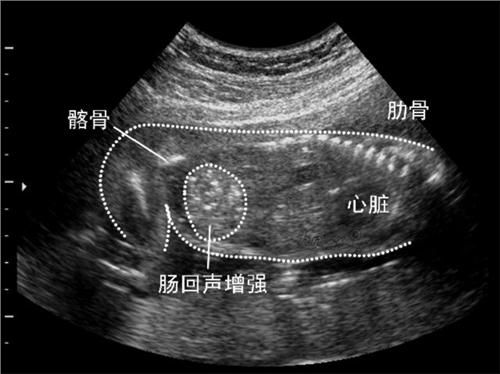

第三,大变形筛查不能缺少经过了前两关之后,孕妈妈是不是以为能大松一口气了呢?可是还有着孕中期的大变形筛查,这也是不能缺少的一个检查。经过这样的检查,爸爸妈妈就可以明晰的对孩子有一个全面的了解,比方他的生长发育以及羊水状况等等。孩子身上有没有呈现变形,他的生长状况是否健康,从这一次的筛查中也可以到达八成的检出率。